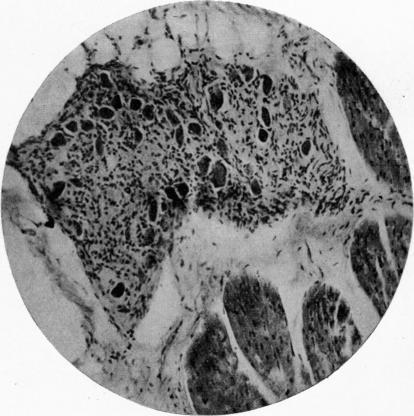

The Auriculo-Ventricular Bundle in Mammals.

J Anat. 1921 Jul;55(Pt 4):269-85.